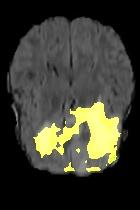

Current unsupervised anomaly localization approaches rely on generative models to learn the distribution of normal images, which is later used to identify potential anomalous regions derived from errors on the reconstructed images. However, a main limitation of nearly all prior literature is the need of employing anomalous images to set a class-specific threshold to locate the anomalies. This limits their usability in realistic scenarios, where only normal data is typically accessible. Despite this major drawback, only a handful of works have addressed this limitation, by integrating supervision on attention maps during training. In this work, we propose a novel formulation that does not require accessing images with abnormalities to define the threshold. Furthermore, and in contrast to very recent work, the proposed constraint is formulated in a more principled manner, leveraging well-known knowledge in constrained optimization. In particular, the equality constraint on the attention maps in prior work is replaced by an inequality constraint, which allows more flexibility. In addition, to address the limitations of penalty-based functions we employ an extension of the popular log-barrier methods to handle the constraint. Comprehensive experiments on the popular BRATS'19 dataset demonstrate that the proposed approach substantially outperforms relevant literature, establishing new state-of-the-art results for unsupervised lesion segmentation.